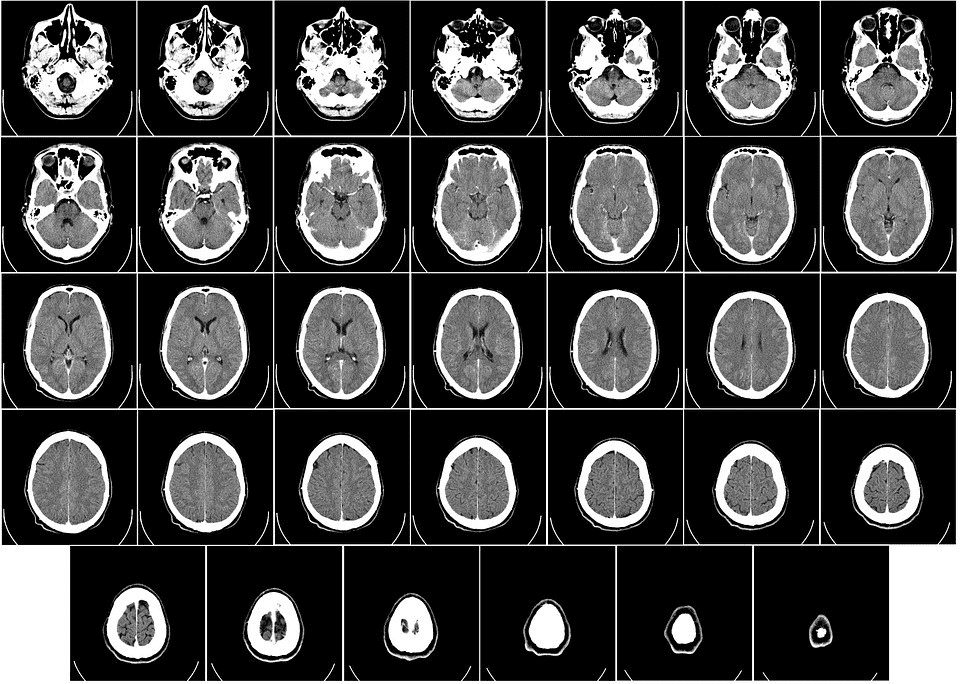

Durante a realização do exame, o paciente fica dentro do tomógrafo (que é o equipamento utilizado para a tomografia), para que sejam lançados feixes de raios-X e formadas imagens em 3D, de diferentes ângulos e nítidas para um diagnóstico preciso.

O que pode ser detectado na Tomografia Computadorizada?

- Doenças no crânio: traumas, infecções, hemorragias, hidrocefalia, aneurismas ou nódulos.